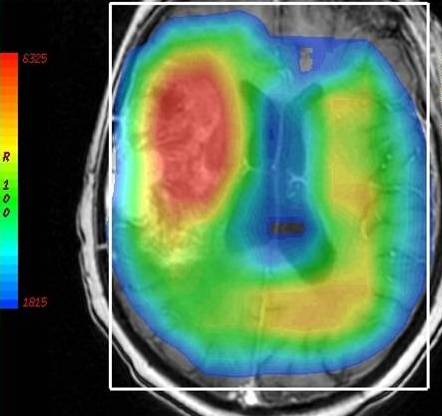

CT Perfusion scan for Radiology

How it works: CT Perfusion evaluates how well blood is flowing to the brain. A small bolus of iodine based intravenous contrast is injected rapidly through a vein, and then multiple low dose CT scans are taken through the same area of the brain to evaluate how the contrast bolus flows through a portion of the brain over time. The data is then processed with advanced perfusion software.

Equipment: Perfusion studies are usually performed on a Philips 64 or 256 channel CT scanner. OHSU is an ACR accredited CT facility.

Benefits: CT Perfusion is a fast, minimally invasive method of evaluating cerebral perfusion.  Reasons for the exam include evaluation of brain perfusion after stroke, temporary ischemic attack (TIA), and/or occlusion or narrowing of a major intracranial vessel.

Exam Preparation: Preparation for a CT perfusion study is the same as for a CT angiogram study. The technologist will interview you for contraindications to contrast such as allergy or kidney problems. If you have had an allergy to iodine based contrast in the past, you should discuss this with your physician before the study. In some situations, an alternative imaging method may be considered, or you may receive medication that needs to be taken before the study to reduce your risk of reaction.  In some situations, kidney function labs may also be checked before your study.  An IV will be placed, usually in the arm.

What to expect: Once you are positioned on the table and the contrast injector tubing is attached to your IV, a localizer scan will be taken, which takes a few seconds. The actual perfusion scan then takes 50 seconds. It is very important that your head remains still during the scan time.  The technologist will check the images before you leave the room. In some situations, a non contrast CT or CTA study will be performed first. If a CTA is performed first, you will have to wait about 10 minutes between CTA and perfusion scans, to let the first bolus of contrast dissipate.  After you have left, the perfusion data will be processed and analyzed, and a board certified neuroradiologist will review the study.

Adverse reactions to contrast materials are uncommon, but can range from mild to severe. Severe reactions are very uncommon. Further information about the risks and benefits of x-rays and contrast material can be found here.

Recent FDA publications have warned of the risks associated with high x-ray doses administered during CT perfusion exams at certain facilities. OHSU uses the latest technology to reduce the x-ray exposure as much as possible while maintaining a high quality examination.

Content by Dr. Louis P. Riccelli